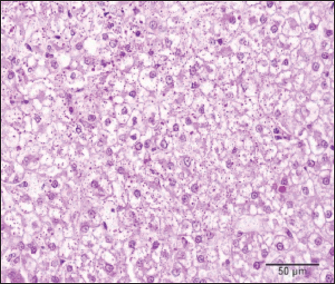

For histopathology, tissue samples were placed overnight in 10% neutral buffered formalin, routinely processed through different grades of alcohols and xylene in a tissue processor (STP 120, Microm, Spain), and embedded in paraffin blocks in a tissue embedding center (EC 500, Myr, Spain). A thin section (4 micrometers) cut at a microtome (RM 2145, Leica, Germany) and stained with hematoxylin and eosin and periodic acid-shiff (PAS) stains was examined under the light microscope (BX-51, Olympus, Germany) by two pathologists. Microscopic examination revealed a multinodular, well-demarcated mass characterized by a solid growth of neoplastic hepatocytes consistent with CCHCC. The neoplastic cells were oval-to-polygonal with clear-to-highly vacuolated cytoplasm and mostly central round nuclei with one small nucleolus (Fig. 4). Moderate anisocytosis, a small number of larger nuclei, and rare mitotic figures were observed. Multifocally, small nodular neoplastic foci were present near the main neoplastic nodules. The remaining hepatic parenchyma surrounding the neoplastic nodules exhibited varying degrees of hepatocyte vacuolation and sinusoidal congestion. Numerous small purple droplets of glycogen were visible in the cytoplasm of neoplastic cells on slides stained with PAS staining (Fig. 5).

Fig. 4. Liver, dog: solid nodular growth of clear neoplastic cells with central round nucleus effaces adjacent vacuolated hepatocytes. Hematoxylin and eosin, 40×.